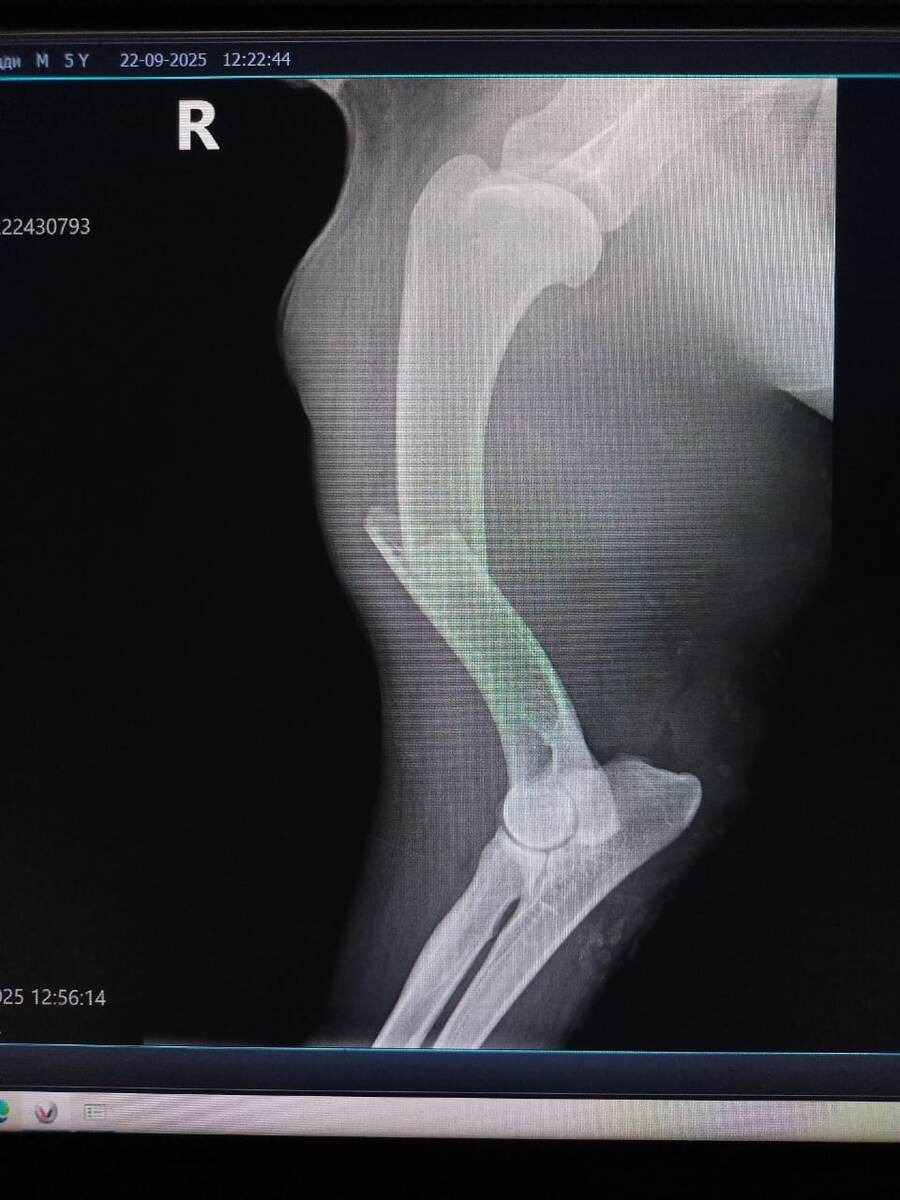

Сегодня возили в клинику "малыша" Гами. Олег Николаевич решил, что имя ему это не подходит. Гами - мишка маленький, а наш большой, 55 кило. И переименовал его в Тедди.

У Тедди переломы обеих передних лап.

Одна лапа - перелом со смещением.

Вторая лапа висит как тряпочка. Кость раздроблена.

Нужно оперировать обе лапы. На раздробленную нужно ставить аппарат Илизарова.